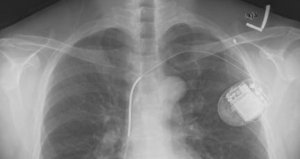

It’s nail-biting time for hundreds of thousands of patients worldwide who have had a Riata defibrillator implanted next to their hearts (79,000 in the U.S., 5,300 in Canada, 4,000 in Australia – just for starters). The recent news about the Riata recall might feel like being told you now have a ticking time bomb inside your chest. Trouble is, you just don’t know if that time bomb will start firing when it shouldn’t, or fail to fire in time to resuscitate your heart when it should.

In December 2011, following reports of premature erosion of the insulation around the electrical conductor lead wires in these devices, the FDA ordered an urgent Class 1 recall (the most serious type of recall) of all Riata and Riata ST Silicone Endocardial Defibrillation Leads manufactured by St. Jude Medical Inc. Here is the FDA recommendation to all patients with these Riata devices implanted in their bodies:* Continue reading “ICD warning: defective defibrillator leads recalled”